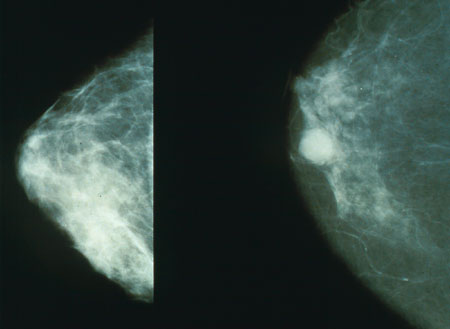

Oct 2021 – Jan 2024- FDA trial technical execution for Mia breast cancer screening AI

- 275,000+ cases validated across 7 sites in 2 countries

Technical writing on reliable agentic systems, applying control theory and clinical AI deployment lessons to multi-agent error propagation. Draws on firsthand observations of radiologist-AI interaction patterns during Kheiron mammography deployments.

Generalisable deep learning method for mammographic density prediction across imaging techniques and self-reported race